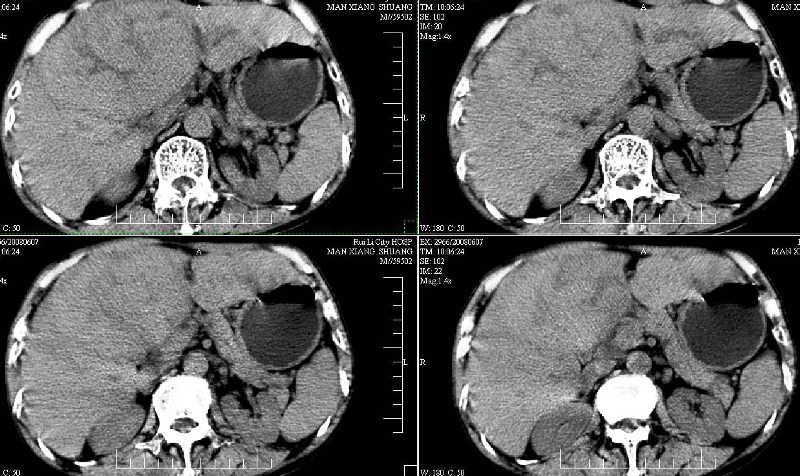

标题: CT13937:M,42A.腰疼一周。

dr:l4骨质破坏,转移可能。

胸部摄片未见异常。临床医生体检发现上腹部饱满。

ct:肝癌腰椎转移。临床医生:肝脏、骨转移,肿瘤来自?前列腺?!

支持肝癌腰椎骨转移

1、肝癌。

2腰椎转移。